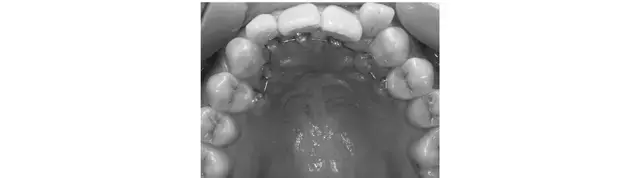

歯の裏側にブラケット(ワイヤーを通すための装置)とワイヤーを装着。部分的な矯正も可能で、強い力で歯を効率よく動かせるうえ、装置が目立たないことがメリット。ただ表側に比べ期間が長く費用も高め。取りはずし不可なので、歯周病のリスク予防に、矯正中はよりてねいな歯磨きを。目安は部分矯正で¥440,000〜。